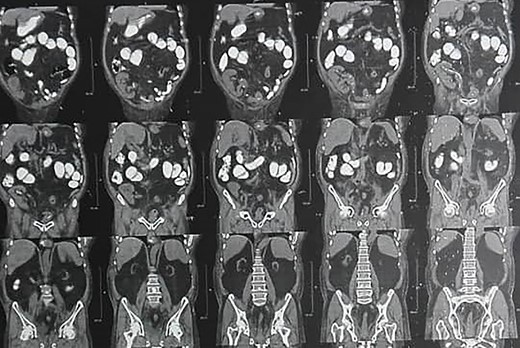

A 71-year-old man, who had received renal transplantation 10 years ago, presented with bladder tumor. Transurethral resection of bladder tumor revealed muscle-invasive BCa. After refusing surgery, he received chemotherapy. Due to no response to chemotherapy, he was referred to us. In primary evaluation, serum creatinine was 1.9 mg/dl (glomerular filtration rate (GFR) = 37 ml/min/1.73m2). Computed tomography (CT) scan revealed mild-to-moderate hydronephrosis of transplanted kidney and two small and atrophic native kidneys with no evidence of tumor metastasis (Fig. 1). In cystoscopy, a 5–6-cm sessile mass was detected in the right bladder wall with involvement of transplanted ureter orifice. Trans-urethral resection of the tumor was performed, and pathologic evaluation revealed high-grade urothelial cell carcinoma with muscularis propria involvement. After counseling, the patient decided to undergo RC.

Preoperative CT scan shows mild-to-moderate hydronephrosis in transplanted kidney and two atrophic native kidneys.